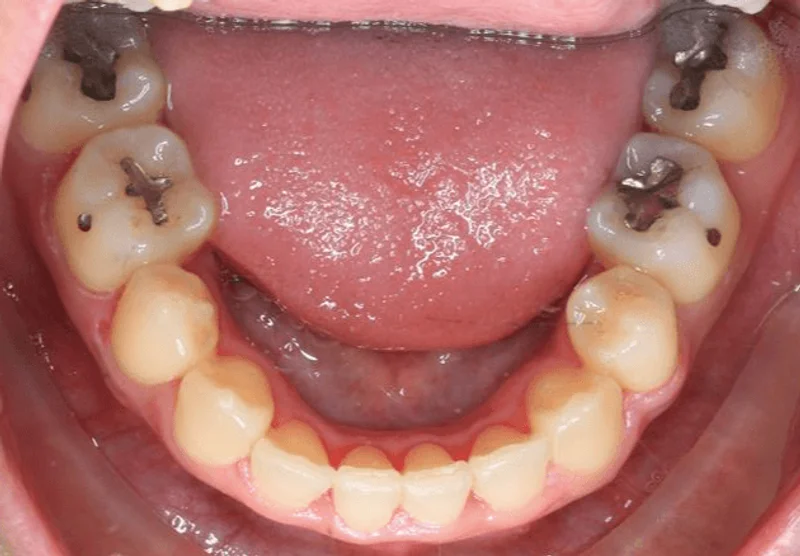

Lower Occlusal

Lower Occlusal - After Treatment

After